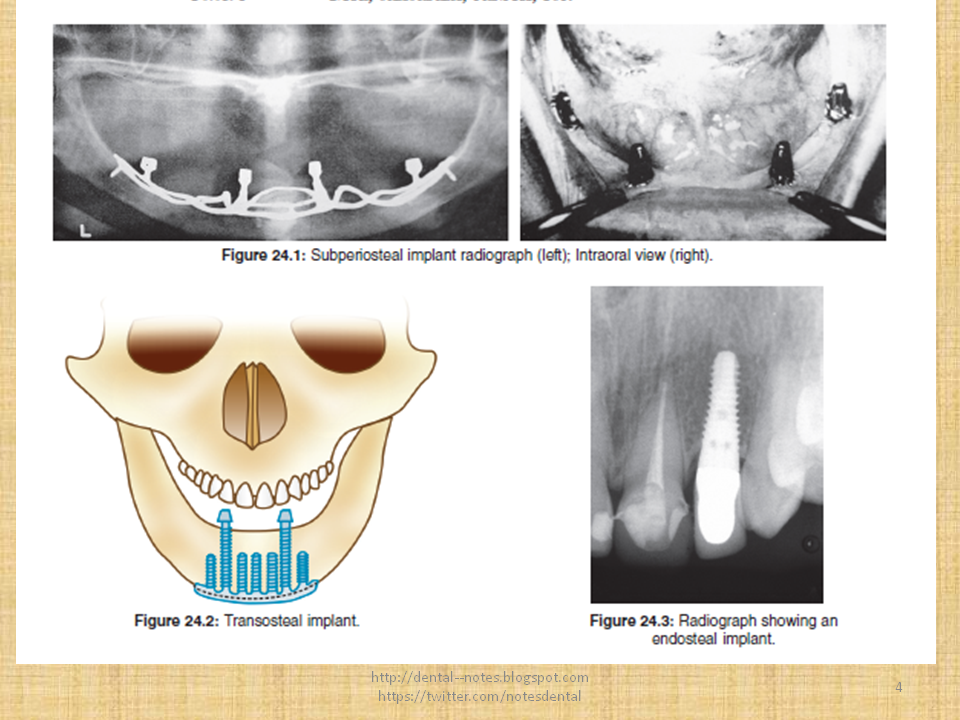

Dental Notes Dental Implant Materials NOTES (new)